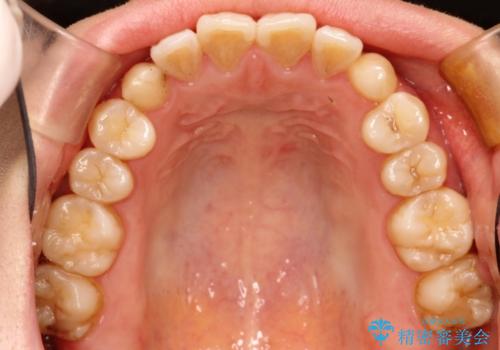

初診時の歯並びの状態としては、上下ともに前歯部に限局した軽度ののがたつき(叢生)がある状態でした。

主に歯列弓の拡大とディスキング(歯と歯の間に隙間を作る処置)を行い叢生を改善しました。

矯正装置としてはマウスピースを使用しています。